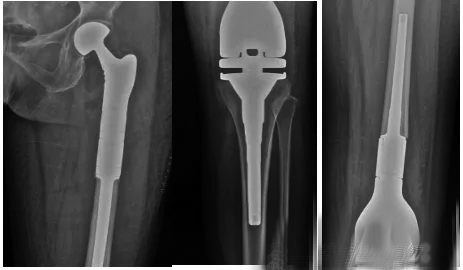

原发性恶性骨肿瘤会致残,甚至造成患者死亡。随着技术的发展,保肢治疗已成为原发性恶性骨肿瘤患者的主要手术方式。随着原发性恶性骨肿瘤的规范化治疗,这类患者的5年生存期已达到50%~80%。人工假体能够较快恢复骨骼的连续性和关节功能,得到了医务工作者的青睐,具有术后即刻稳定、患者可早期负重、短期和长期术后功能较好的优点。 下面,我向大家简单介绍一下目前临床上使用的人工假体。 定制型人工假体:此类假体在最初用于肿瘤切除后骨缺损的重建,需要术前根据患者的影像学检查结果进行个体化定制,术前需要反复测量数据,多次和工程师沟通;存在术中假体尺寸不合适,需要调整截骨范围,甚至无法完成手术的风险,现在较少使用。目前,定制型人工假体主要用于特殊人群(年龄小、无组配型人工假体、假体髓针过短而需要特殊设计者)和经济困难的患者,是组配型人工假体的一个补充。 组配型人工假体:随着定制型人工假体应用的增多和生物固定技术的发展,根据瘤段骨的特点术中组装合适规格的假体逐渐成为主流。主要优点包括可对多个组配模块进行术中调换组装,后期翻修时仅需更换受损部件。组配型人工假体目前较多地应用于肱骨近端、股骨近端和肿瘤累及膝关节面的患者。 可延长假体:可延长假体主要是为了解决儿童保肢术后双下肢不等长的问题而研发的。目前主要应用的是微创或无创可延长假体,适应证是:预计下肢短缩>3厘米,上肢短缩>5厘米,或者年龄<11岁的女孩和年龄<13岁的男孩。这类假体主要的远期并发症是无菌性松动。随着患儿身高的不断增长,骨骼的生长会使骨骼横径和髓腔横径增大。另外,患儿的依从性差,活动量大,因此松动率较高,待其成年后可更换为普通成人型人工假体。由于延长过程中多次手术造成的瘢痕,及延长后髌腱和股四头肌腱的相对短缩,容易造成关节活动受限。一般建议每次延长0.5厘米~1厘米。 半关节假体:为了避免损伤关节健侧骨骺,有的医院开始尝试在股骨远端和胫骨近端进行半关节置换,保留关节一侧的骨骺,可尽量减少肢体不等长的发生。术中需要精心设计假体长度和关节面大小,并保留和重建周围韧带,术后进行支具保护。经过患者较长时间的康复锻炼,仍可维持膝关节的稳定并取得较高的功能评分。 其他假体:随着对肿瘤生物学、精准截骨的设计和假体研究设计的进展,为了达到更好的功能重建的效果,有的医生会对患者进行带血管蒂和假体的复合创建,保留骨骺的假体重建和精准截骨后3D(三维)打印重建等。 (作者供职于河南省肿瘤医院)